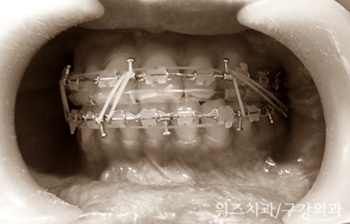

양악수술은 기능적인 회복을 최우선으로 하는 수술이다. ‘악간고정’이란 수술 전에 치아에 부착한 장치를 이용하여 위 아래 턱의 위치를 고정해주는 과정을 말한다. 흔히 입묶음 이라고 말하는 이 과정은 정상적인 교합의 조건을 갖춘 하악골 운동을 유도함으로써 빠른 시기에 턱의 기능이 회복되고 안정적인 위치에 고정되는 것을 도와 수술 후 다시 입이 벌어지는 현상이나, 회귀 성향 등 장기적인 합병증을 예방하는데 도움을 주는 필수적인 과정이다.

턱의 위치가 달라지는 턱교정 수술 이후에 악간고정이 필요한 것은 뼈를 둘러싸고 있는 연조직과 근육도 턱뼈의 변화에 적응하도록 도와야 하기 때문이다. 턱뼈, 연조직, 근육이 모두 새로운 위치에, 수술받은 사람에게 가장 편안하도록 자리 잡도록 돕는 과정인 것이다. 특히 하악을 고정하지 않는 방식인 IVRO 수술법이나, SSRO 법 모두에서 악간고정을 한 환자의 수술 경과가 더 좋았다는 교정과 의사의 발표도 있었던 만큼 악간고정은 안정적인 회복을 위한 좋은 치료 방법이다.